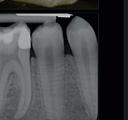

material matters

To use clear aligners to their greatest potential, it’s important to look briefly at their treatment ceiling. Complex cases that include severe bite issues, large gaps, or severe crowding may make this form of treatment less suitable, instead requiring traditional fixed braces. The literature has also cited distalisation, rotation and extrusion as some of the more difficult movements to carry out successfully with clear aligners, and whilst it is not impossible to achieve these results, a relevant case may prompt the need for an alternative treatment approach.

However, recent developments in the materials used to create clear aligners as well as clinical approaches have improved predictability in a wider range of cases.

Polyethylene terephthalate glycol (PETG) materials have been the solution of choice for many complex designs due to their durability, high impact strength and resistance to chemical changes. With impressive mechanical and optical properties, it’s easy to see why they are increasingly preferred.

The future of complex clear aligner cases could lie in shape memory polymers (SMPs), sometimes known as actively moving polymers. This material offers the ability to revert to an original shape when achieving a necessary transitionary trigger, such as a certain temperature for a designated time period. During a treatment cycle, the SMP-based aligner could be subjected to such a trigger, reverting to a predefined shape, and in turn generating forces which can produce orthodontic tooth movement. When designed to harbour multiple aligner shapes within its form, it could reduce the number of aligners used during orthodontic treatment and achieve complex corrections sooner.

Step by step

When tackling a complex case suitable for aligner therapy, treatment is most effective when the dentist creates an efficient and actionable treatment plan. Therefore, one of the most important skills for a clinician providing clear aligners for complex cases is an understanding of how to implement staging.

Those that have prior experience in orthodontics may know that staging refers to the breakdown of an intended movement of teeth in a sequential manner, with the use of aligners. This segmented approach

allows for the close control over linear and rotational movements over time, with each new aligner achieving a specific step that gets a patient closer to their end goal. In complex cases, staging orthodontic tooth movement is essential and can be used to attain better treatment outcomes.

When used in the treatment of severe crowding, staging has provided no significant differences in results when compared to fixed brace treatments, including in case duration. One 2022 study broke up the process into three overarching stages of ‘decrowding‘, ‘space closure’ and ‘fine-tuning’. This allows for targeted movement of the crowded anterior teeth, before achieving a class I canine and molar relationship, and making final adjustments, such as overcorrections – recommended by many in case of possible relapses – and closures of any residual spaces.